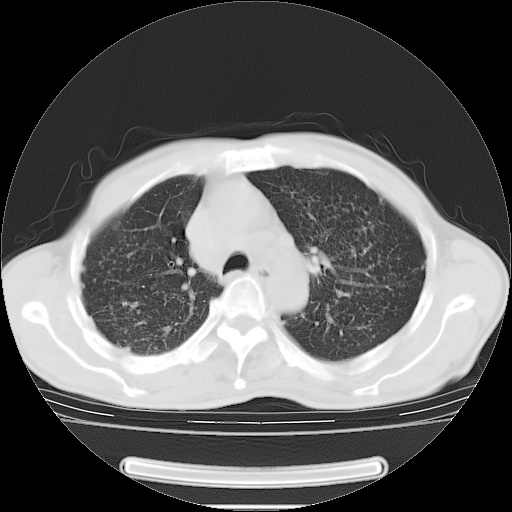

男性患者,63岁。右侧胸背部疼痛2月,加重一周。

考虑:右肺中央型肺癌并右肺下叶不张;两肺尖继发性肺结核。

还有纵隔多处肿大淋巴结及肋骨的改变、两肺多发结节灶。

右肺下叶支气管狭窄闭塞,右下肺不张,气管前间隙淋巴结肿大,两上肺散在分部粟粒灶,沿肺血管支气管束分部,血管支气管束走形较为光滑。考虑右肺中心型肺癌合并肺不张,纵隔淋巴结转移,两上肺癌性淋巴管炎